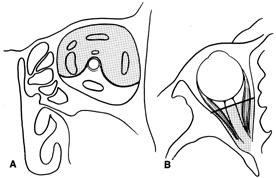

Fig. 25. A,B. Coronal (A) and axial (B) CT scans demonstrating well-encapsulated mass posteriorly in the superonasal orbit. An excellent alternative to transcranial orbitotomy for this lesion is an anterior approach via a vertical-lid splitting incision.

VERTICAL-LID-SPLIT SUPERIOR ORBITOTOMY

The upper eyelid crease incision gives excellent access to the peripheral superior orbital space. However, lesions that lie intraconally are difficult to approach with a transverse lid crease incision as dissection must be performed medial to the medial horn of the levator muscle to avoid transecting and disinserting the levator aponeurosis and Müller's muscle. However, vertically splitting the upper lid allows a vertical separation of the levator aponeurosis and Müller's muscle and does not disinsert it from its normal insertions on the tarsal plate. This approach provides an excellent exposure of the superomedial orbit and is useful for approaching lesions that lie medial to the optic nerve.26 In this situation, it is often an attractive alternative to a transcranial superior orbitotomy, which might otherwise be required (Fig. 25).